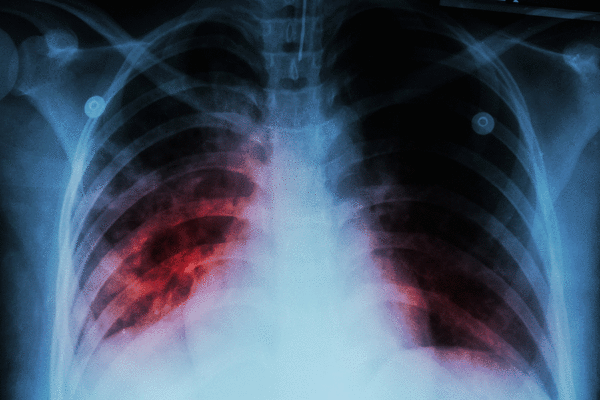

Tuberculosis is an infectious disease caused by bacteria that typically infects the lungs after being spread by coughing, according to the World Health Organization. About 1.2 million people died from TB in 2024 among more than 10 million new infections; roughly one in four people worldwide carries the bacteria without symptoms, while 5–10% develop active disease. Babies and children are at a higher risk of developing the disease if they are infected.

Common symptoms include prolonged coughing, sometimes with blood, chest pain, weakness, fatigue, weight loss, fever and night sweats. The disease is usually treated with antibiotics and can be fatal without treatment.